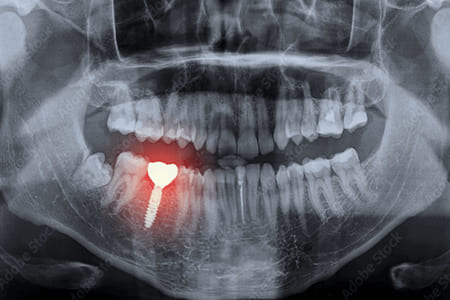

インプラントの周囲からの排膿や出血の有無を、「プローブ」という器具で確認します。その後に、歯科用CTなどを用いて画像診断を行います。

インプラント周囲炎の症例

症例の詳細

| 治療名称 | 前歯部インプラント周囲炎に対し、外科的・補綴的アプローチを行なった1症例 |

|---|---|

| 費用 | およそ400,000円(税別) |

| 治療期間 | 6ヶ月 |

| 患者様の主訴 | 前歯のインプラントがぐらつく |

| 治療を行ううえでの注意点 | インプラント周囲炎は未知の部分が多く、完全な治療方法が確立されていません。しかし、主な原因として細菌感染症が考えられるので、さまざまな方法を使って洗浄していきます。綺麗にしていく過程で、病巣となった組織の一部も切り取っていくので、術後に歯ぐきが後退するような形で治癒する可能性もあります。 |

| 治療方法 | こちらの患者様は他の歯科医院にてインプラントの治療を行い、その後のメインテナンスにしばらく通わなかったためインプラントの周囲に汚れが付着し、インプラントの歯周病である「インプラント周囲炎」になってしまいました。実際ぐらついていたのはインプラントではなく、そこに接続されていた土台にあたる部分だったので、感染部分を含めて除去し、インプラントは残したまま被せ物を再作成していきました。 |